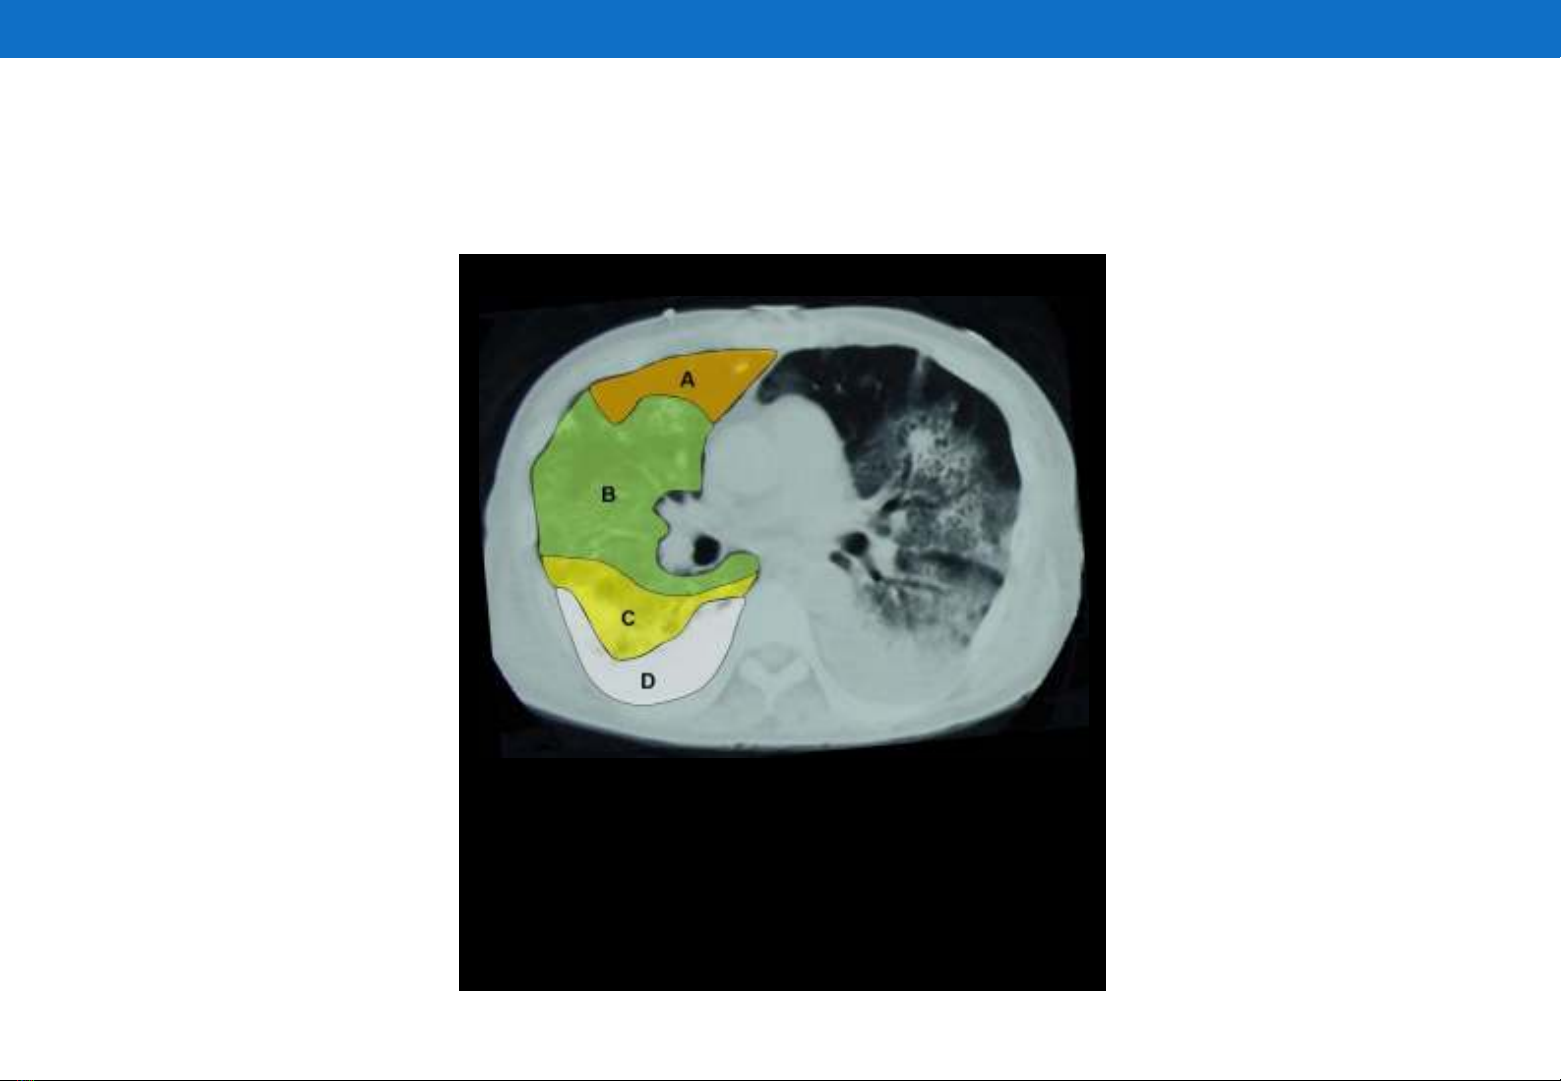

Tổn thương phổi trong ARDS là không đồng nhất

A = Alveolar overdistension

B = Normoventilation

C = Tidal recruitment

D = Alveolar collapse